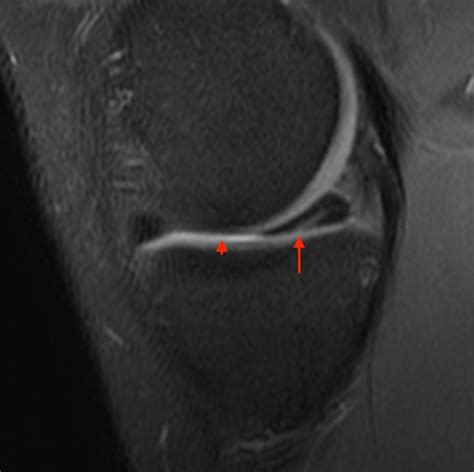

• Magnetic Resonance Imaging (MRI) to provide detailed images of the meniscus and surrounding structures. MRI is particularly useful in identifying the location and extent of the tear.

In some cases, an arthroscopy may be performed to directly visualize the meniscus and confirm the diagnosis. This minimally invasive procedure involves inserting a small camera into the knee joint through a tiny incision.